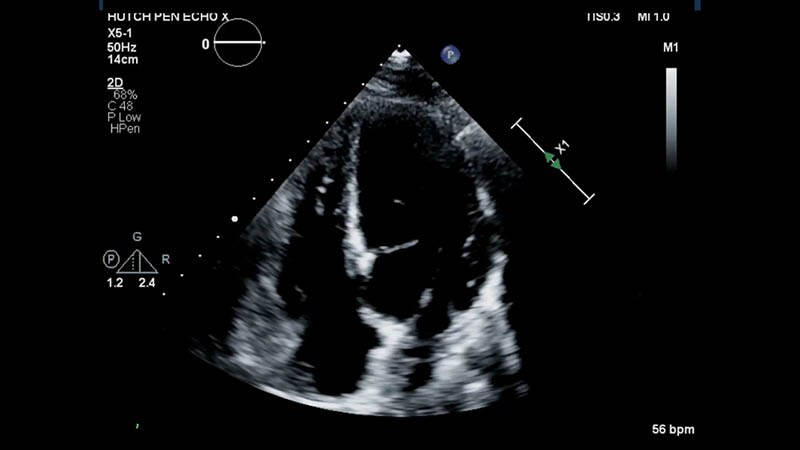

CV Imaging